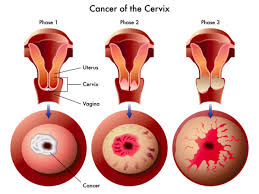

قیمت: 88٬000 تومان - دسته بندی فایل: تحقیق

قیمت: 88٬000 تومان - دسته بندی فایل: تحقیقپاورپوینت بیماریهای داخل اپیتلیال سرویکس و کانسر سرویکس (ppt) 64 اسلاید

فروش ویژه پاورپوینت حرفه ای بیماریهای داخل اپیتلیال سرویکس و کانسر سرویکس / تعداد اسلاید : 64 اسلاید